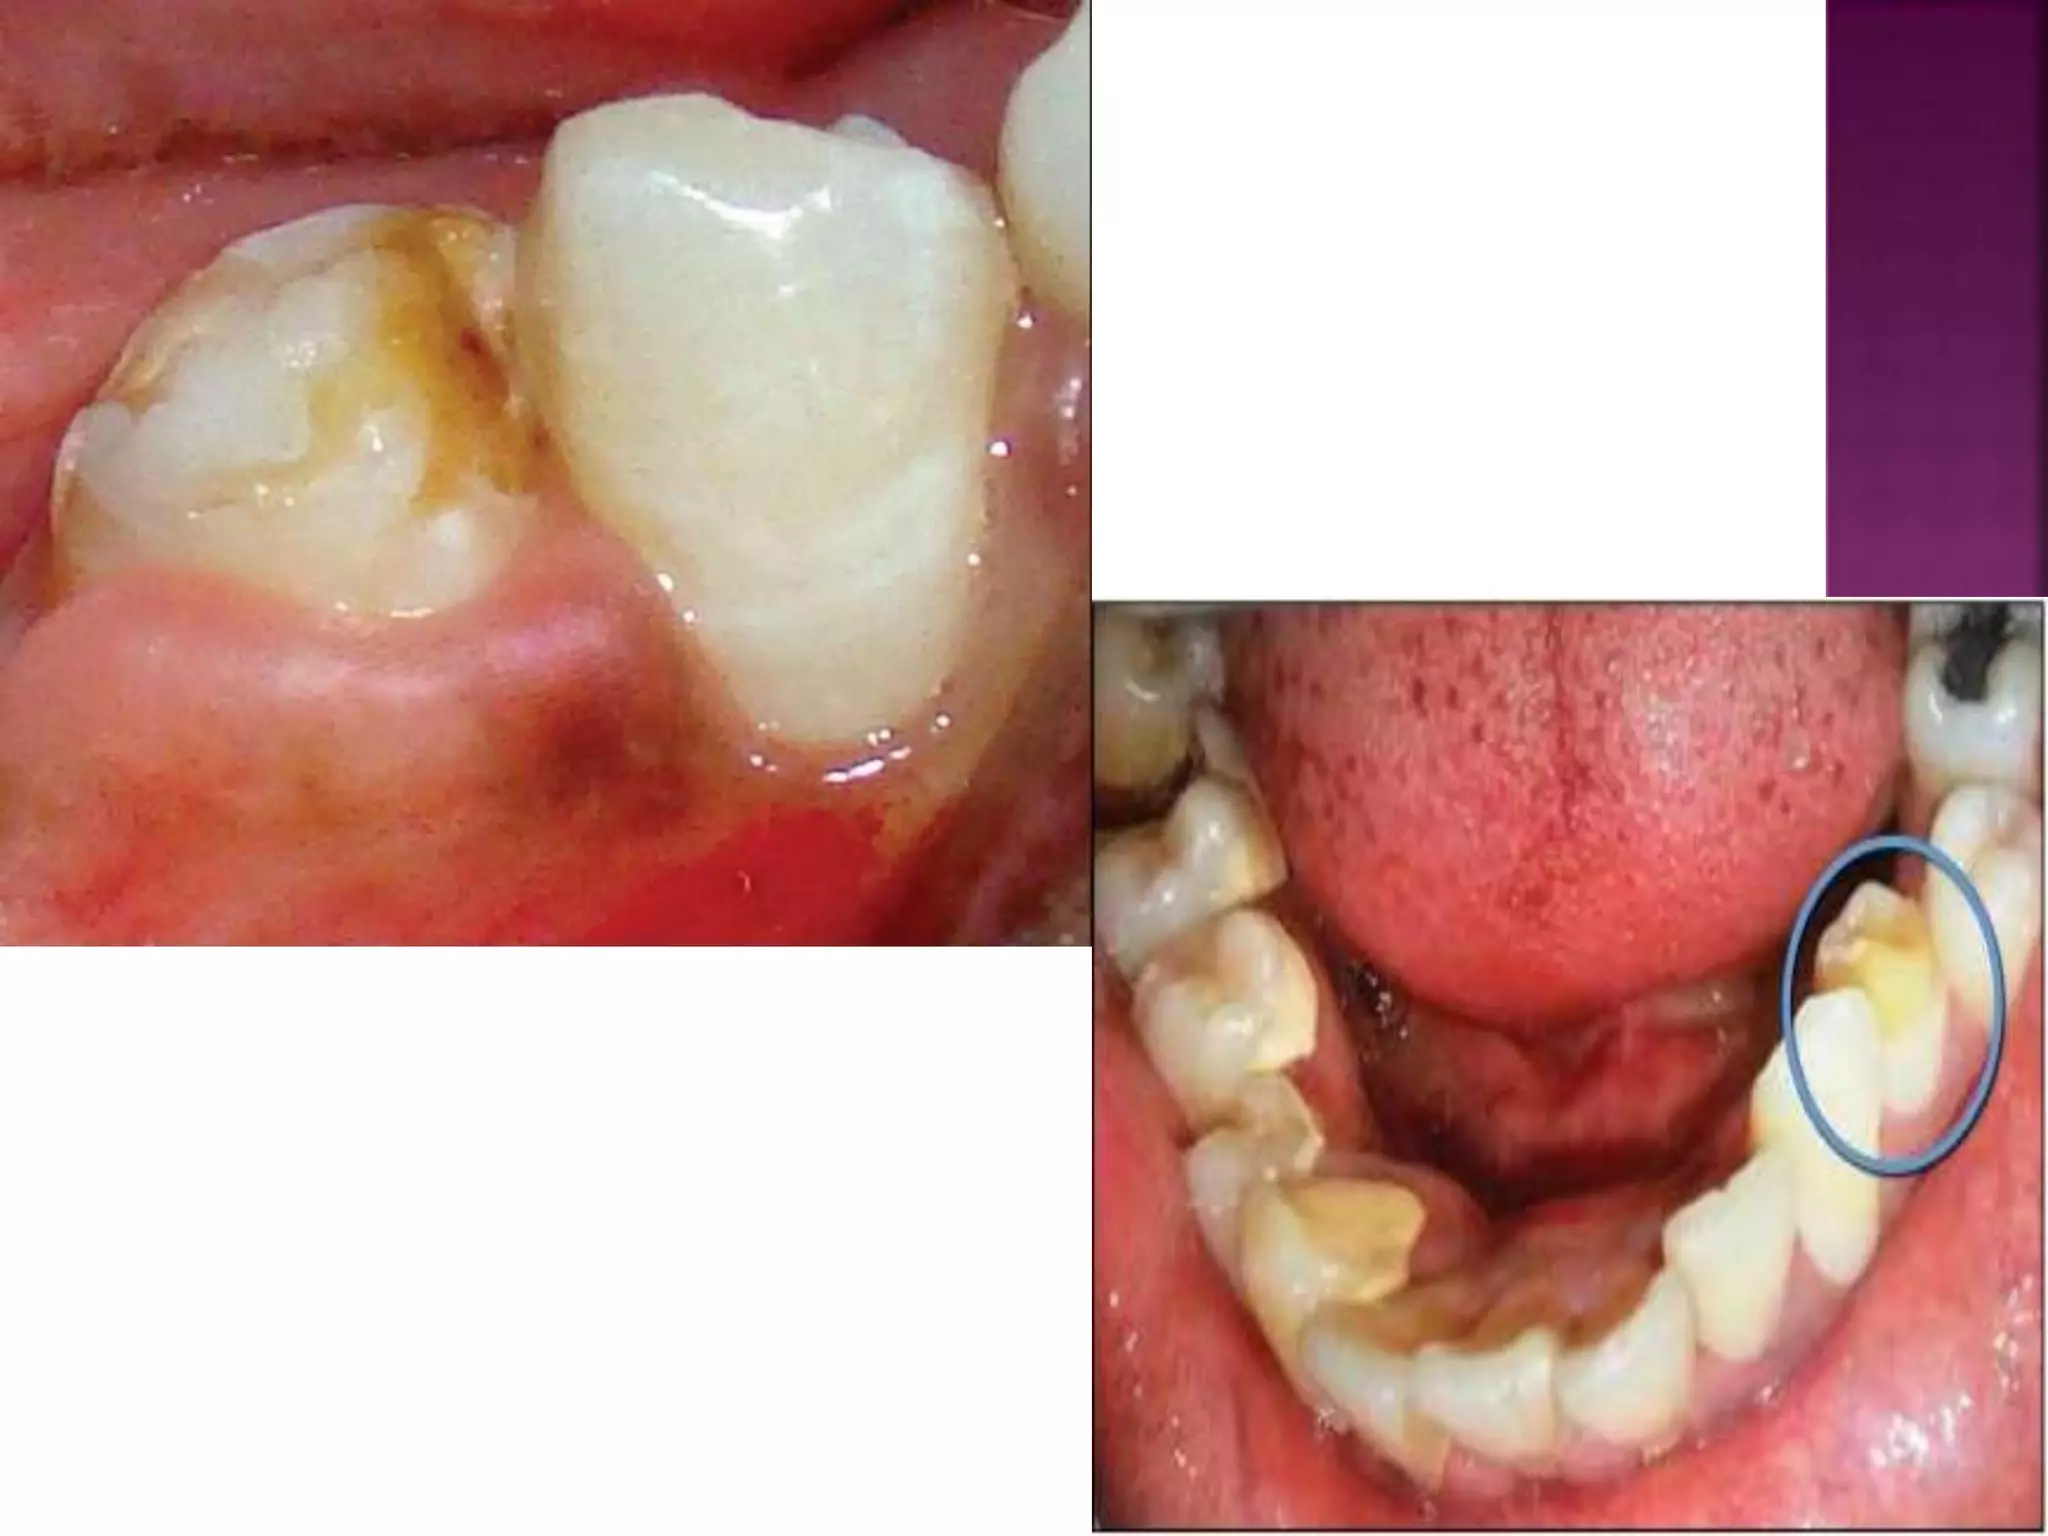

6. TURNER’S HYPOPLASIA-

 Turner’s Tooth- Localized type of hypoplasia, it

is caused by local infection or trauma and is

called as “Turner’s Hypoplasia” and the tooth

is called as Turner’s tooth.

 Pathogenesis-

A. Local infection- If deciduous teeth become

carious during the period when the crown of

succeeding permanent tooth is formed, then

bacterial infection involving periapical tissues

may occur and this may disturb the

ameloblastic layer of permanent tooth bud,

resulting in hypoplastic crown.

20

B. Trauma- When deciduous teeth have been

driven into alveolus and have disturbed the

permanent bud while the permanent tooth

bud is still being formed then resulting

injury leads to yellowish or brownish stains

of enamel usually on labial surface or as

true hypoplastic pitting effect.

 Site- Most commonly affected teeth are

permanent premolars as deciduous molars are

most frequently affected carious tooth in

primary dentition. lesion.

21

 Appearance- Hypoplasia may be ranging

from mild brownish discolouration of

enamel to severe pitting and irregularity of

crown. Cementum may also be stained

yellowish-brown.